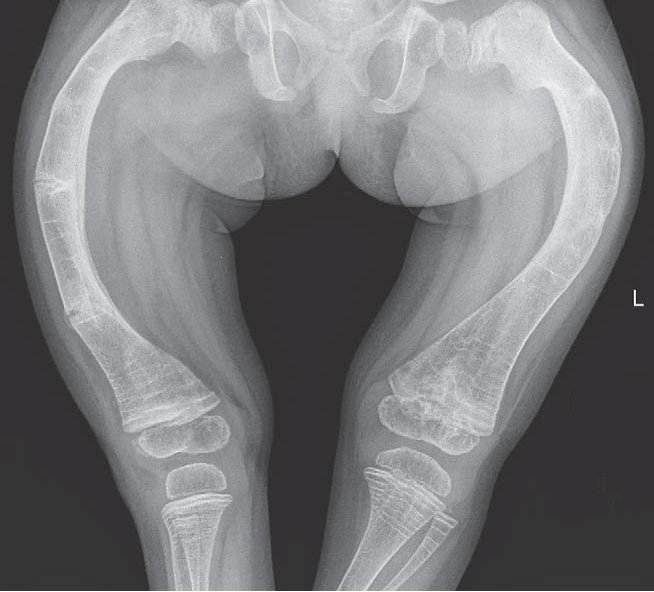

1.4 Bệnh xương thủy tinh

Bệnh xương thủy tinh là một bệnh lý xương phổ biến, đi kèm với sự giòn dễ gãy của xương, giảm khối lượng cơ bắp, và lỏng lẻo các khớp và dây chằng. Các dấu hiệu nhận biết bao gồm:

Cột sống uốn cong